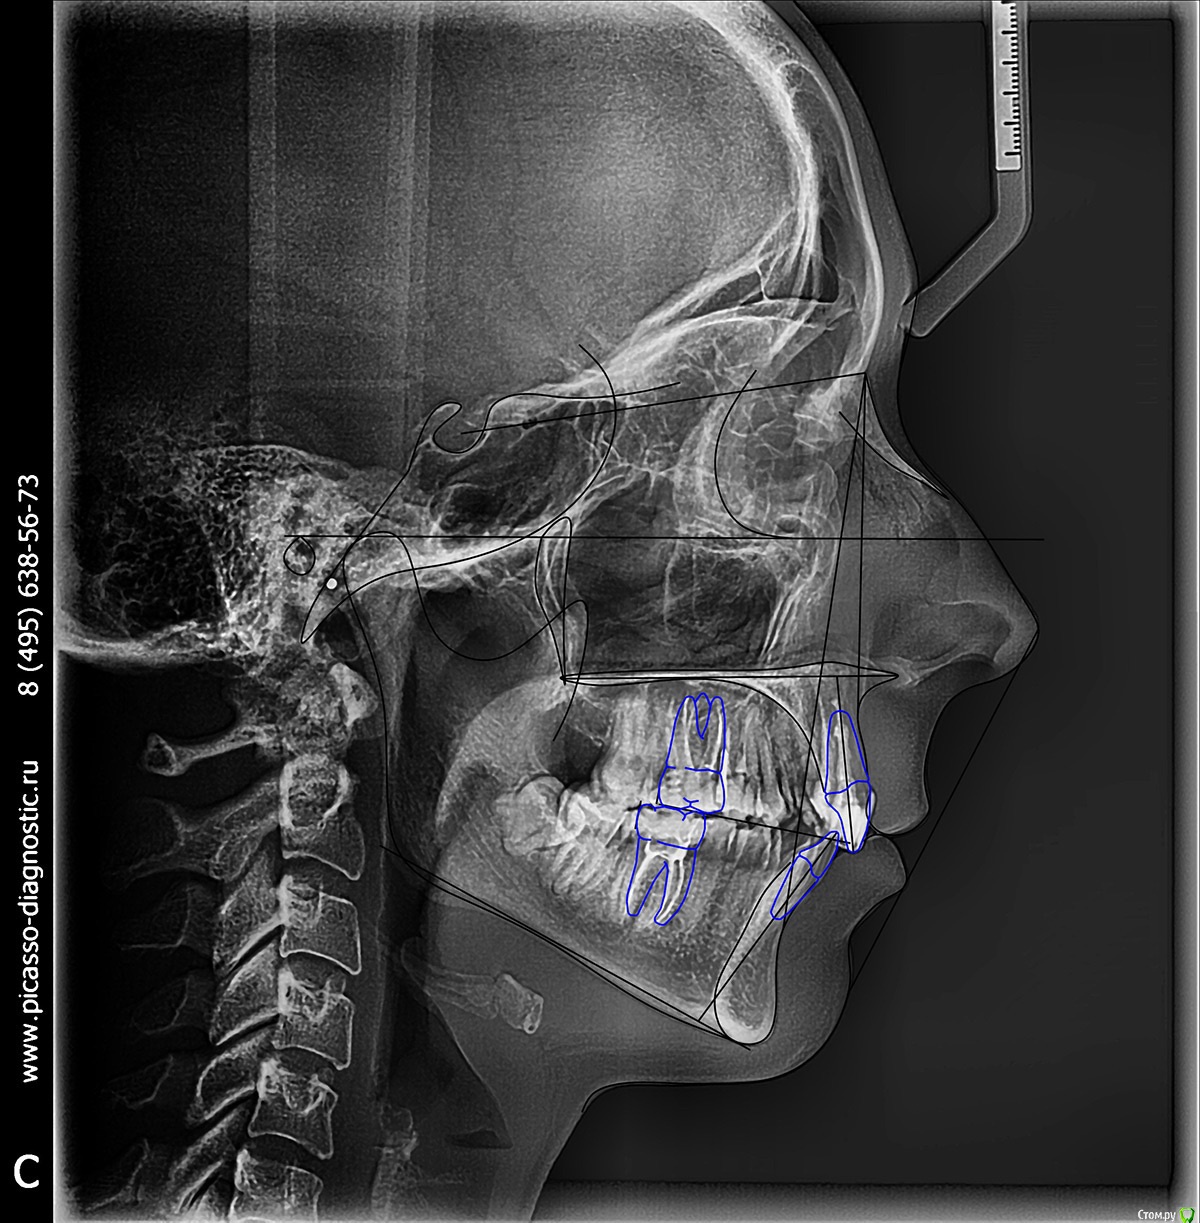

Добрый день ! Мне 29 лет. Ношу брекеты 10 мес. На данном этапе лечения сделали панорамный снимок, чтобы посмотреть ровно ли стоят корни зубов. После этого врач решил переклеить один брекет на клыке ( на снимке его видно слева ). А мне по снимку бросились в глаза , помимо этого клыка, рядом стоящий боковой резец ( он же не нравится мне как стоит и внешне) , и на нижней челюсти : 1- ый премоляр,и рядом стоящие 3 резца. Врач сказал подумать неделю и решить, хочу ли я переклеить или нет какой либо из брекетов,тк дальше они так и останутся. На её взгляд ничего переклеивать , кроме клыка, больше не нужно.

П.с. На нижн. челюсть уже поставили резинки для стягивания щелей. Я так понимаю после этого этапа уже на них брекеты не будут переклеиваться ?

Главный вопрос : Нужно ли мне переклеивать еще какие- нибудь брекеты , опускать или поднимать какой- либо из зубов, чтобы добиться большей эстетики и в дальнейшем правильного прикуса ? Или же не нужно. Заранее спасибо за внимание.